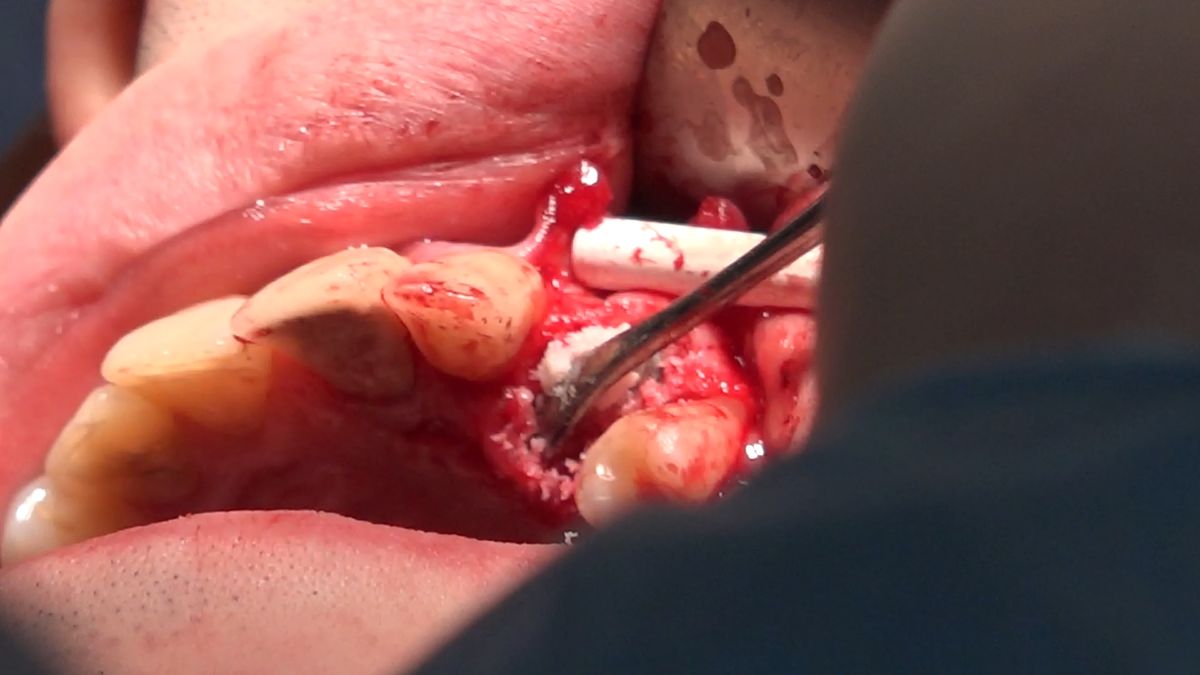

Practiculum Implantologii – Sezon VIIB, sesja 7, dzień 2